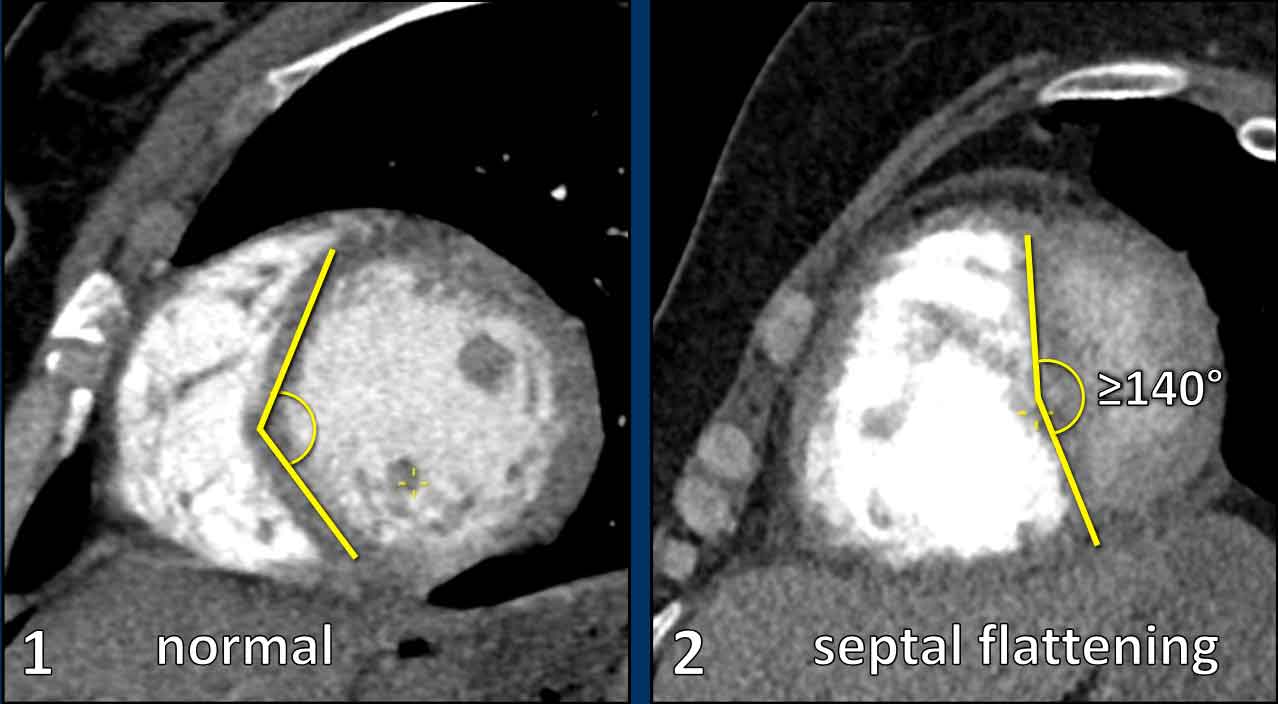

3. Flattened or bowed interventricular septum

Abnormal projection (ie. flattening) of the interventricular septum with an angle ≥140° on a short axis view.

In the short-axis view, a normal left ventricle demonstrates a circular to elliptical configuration.

The interventricular septum contributes to the circular contour of the ventricular wall.

Septal flattening or leftward bowing is indicative of pressure overload and right ventricular dilatation.